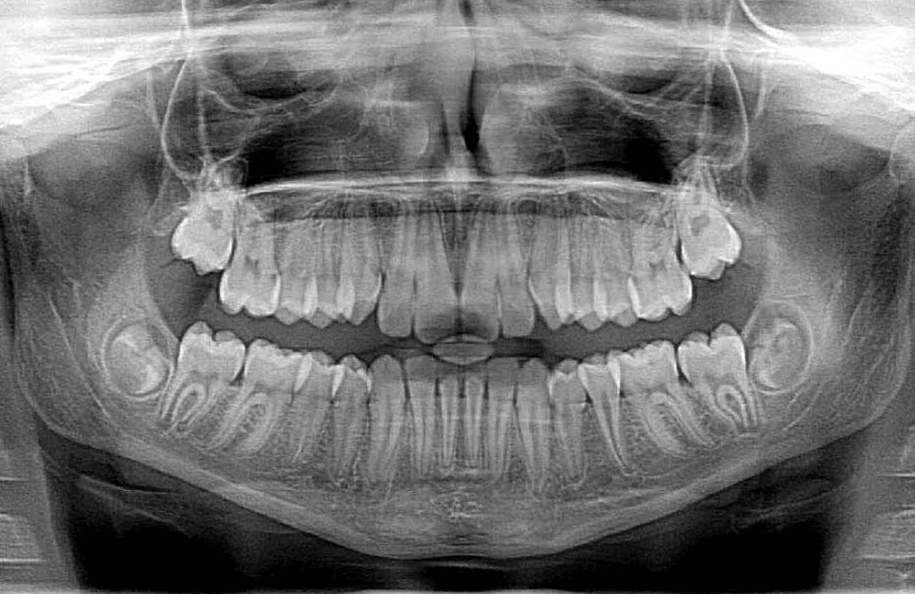

아래 사진과 같이 사랑니가 숨어 있는 경우, 어금니의 뿌리 쪽을 누르기 때문에 이빨 사이 간격이 넓어지고,

음식물이 나도 모르게 끼어 있을 수 있다고 해요.

아래 사진에 맨 안쪽 어금니 사이의 간격이, 다른 이빨 사이의 간격보다 떨어져 있는 것 보이시죠?

저처럼 사랑니가 숨어 자라서 발치를 하지 않는 분들의 경우에는, 저와 같은 유형일 가능성이 높다고 보면 되겠죠?